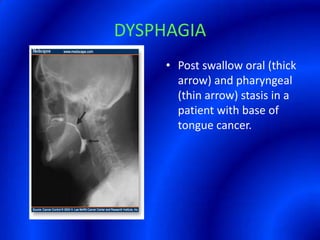

This document provides information about a barium swallow procedure. It begins with an introduction and overview of the embryology and anatomy of the pharynx and esophagus. It then describes the procedure itself, including preparation, technique, views obtained, and indications. Specific conditions that may be examined include pharyngeal and esophageal webs, foreign body impaction, scleroderma, dysphagia, mediastinal masses, and carcinoma. Diagrams are provided to illustrate normal anatomy and various pathological findings.